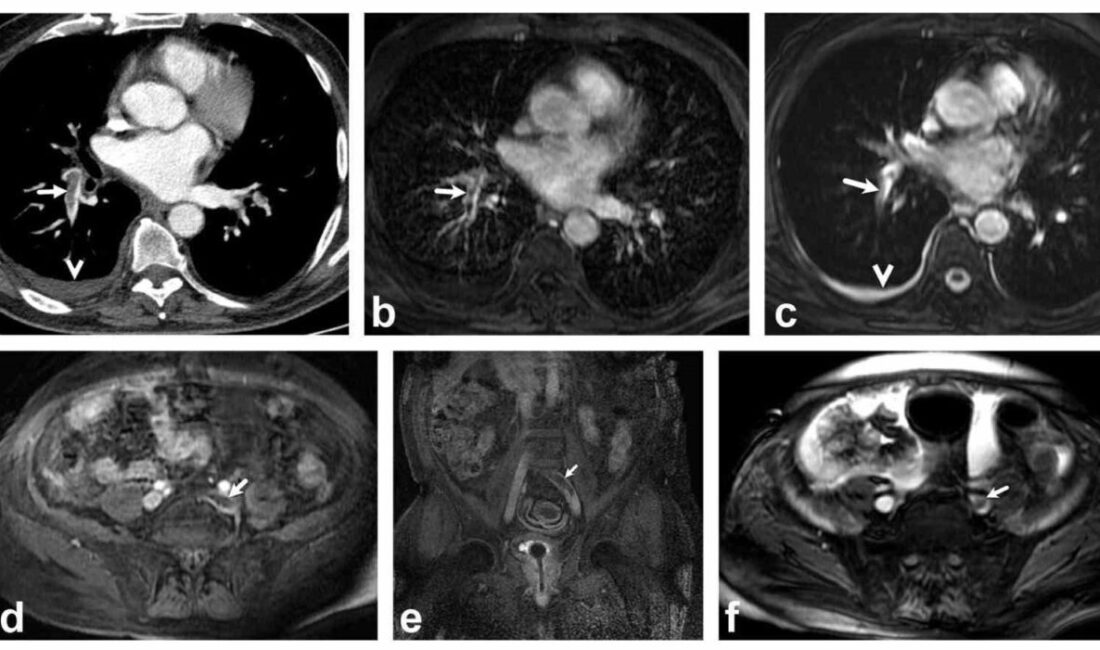

Bir dönem Denizli Tekden Hastanesinde de çalışan ve çalışmalarına ABD’de devam Dr. Nevzat Karabulut ve ekibinin yaptığı, British Journal of Radiology dergisinde yayımlanan “Diagnostic performance of contrast-enhanced and unenhanced combined pulmonary artery MRI and magnetic resonance venography techniques in the diagnosis of venous thromboembolism” başlıklı araştırmada manyetik rezonans (MR) yöntemi kullanılarak hem akciğer damarlarının hem de pıhtının kaynağı olan bacak toplardamarlarının aynı anda, tek bir incelemede değerlendirilebileceği gösterildi. Toplam 44 hastanın incelendiği çalışmada elde edilen sonuçlar oldukça dikkat çekti.

Kontrastlı MR yöntemi, hastaların tamamında akciğer embolisini doğru şekilde tespit ederken; kontrastsız MR yöntemi de yüksek doğruluk oranına ulaştı ve önemli ölçüde güvenilir sonuçlar verdi. Bu bulgular, radyasyon içermeyen MR yönteminin pıhtı hastalığını saptamada güçlü bir alternatif olduğunu ortaya koydu. Özellikle Radyasyon riskinin daha önemli olduğugenç hastalarda ve gebelerde MR’ın güvenli ve etkili bir seçenek olabileceği vurgulandı.